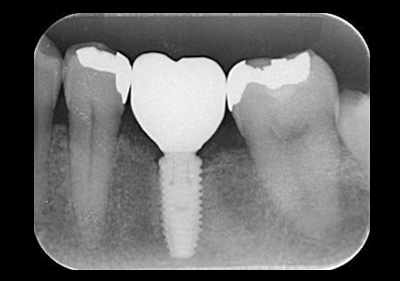

インプラント(骨造成術あり)

費用:50万円

治療期間:12ヶ月

メリット:隣の歯を削らない。歯と同じように噛める。

デメリット:骨、歯肉の状態では外科処置を数回行う場合あり。

治療後レントゲン![]() |